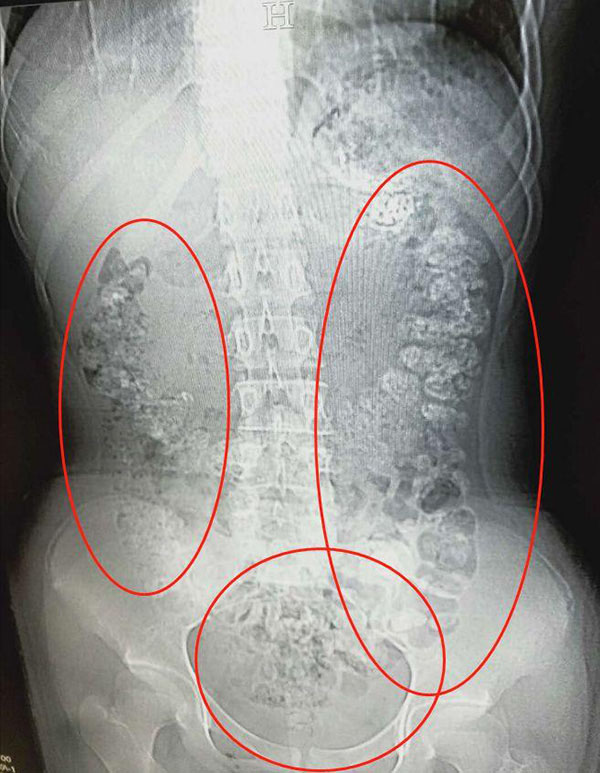

Setelah menjalani CT Scan di bahagian perutnya, doktor menemui sejumlah besar ‘bubble tea pearls’ yang tidak dapat dihadam.

Penemuan itu mengejutkan para doktor yang kemudian menyoal siasat pesakit mengenai perkara itu.

Remaja itu memaklumkan, dia mengambil minuman tersebut lima hari yang lalu. Tetapi Dr. Zhang yang merawatnya berkata, tidak mungkin sejumlah besar ‘bubble tea pearls’ itu diambilnya dalam masa satu hari, bermakna pesakit itu berbohong mengenai pengambilan minuman itu dari ibu bapanya serta meminum minuman itu setiap hari.